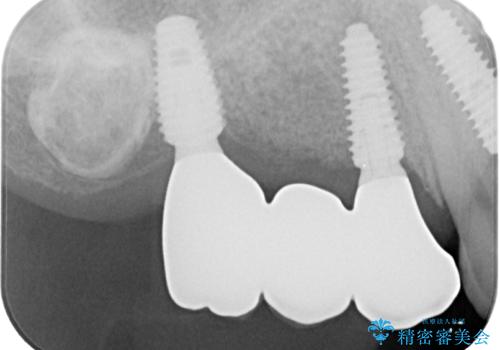

臼歯はもはや咬み合わせに寄与していない状態であり、3歯を抜去してインプラント2本埋入によるブリッジ補綴を計画しました。

抜歯即時埋入インプラントによる補綴治療の特徴は、短期間であることや処置数が少ないことが挙げられます。また、表側の歯肉の陥凹を避けることができるというメリットがあります。しかしながら、今回は歯根破折の程度が酷く、やや膨らみを失うこととなりましたが、スムーズに治療を終えることができました。

臼歯部は前歯以上に炎症が酷く、抜歯即時埋入不可と判断されましたが、従来法よりは短期間で終えることができました。